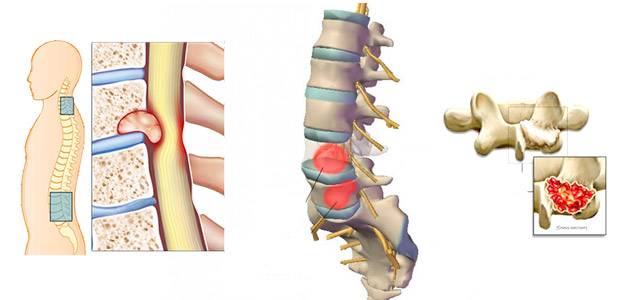

Позвонок Th10: анатомия и фото медицинских иллюстраций